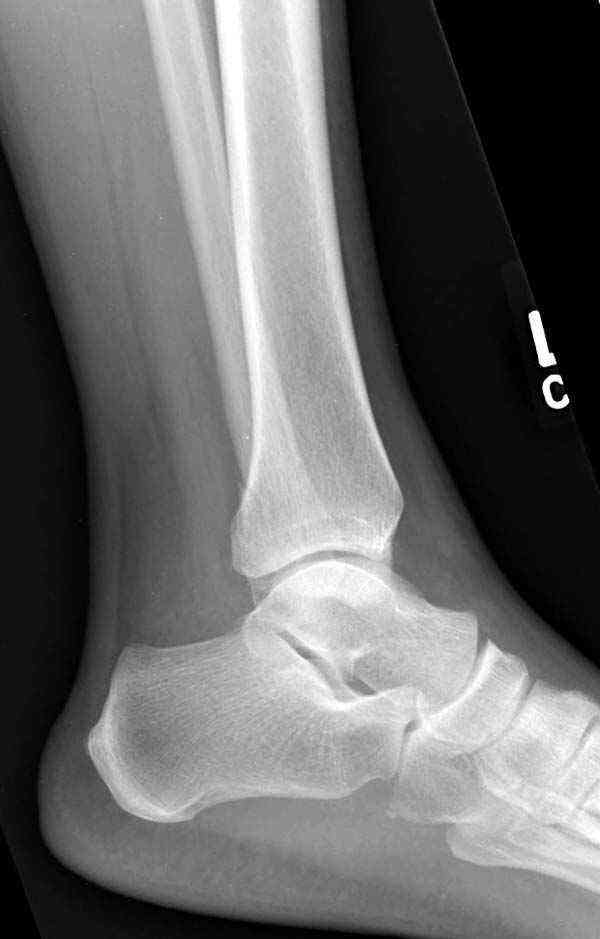

Коллеги правы, что при рутинных переломах достаточным бывает обычные снимки с мортизом. А стрессовые рентгенограммы могут уточнить, есть ли разрыв синдесмоза.

Здесь несколько частных случаев: перелом голеностопа со сравнительными снимками и разрыв синдесмоза, а также медиальная Hook пластина.